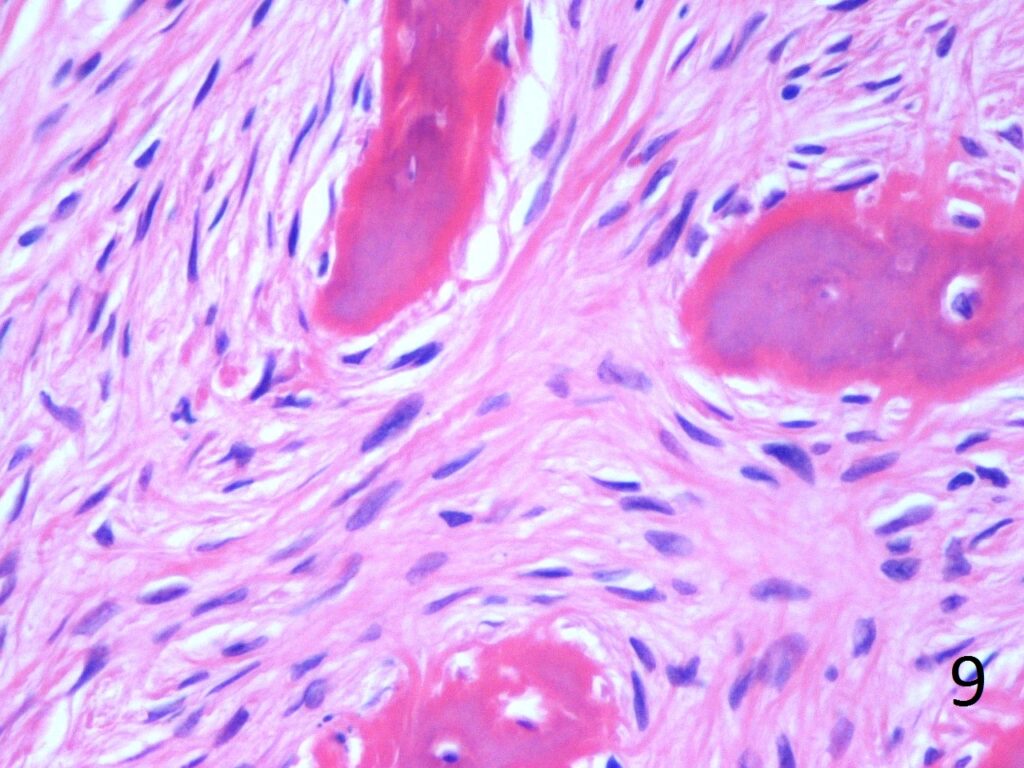

Microscopic

• Combination of bland hypocellular fibrous tissue with small fragments of woven bone without visible rimming by osteoblasts(Fig. 7-8) .

• The trabecule are common referred as Chinese characters, or resembling “Cs”and “Os”. Also may be called Alphabet Soup. This arrangement may mimic the appearance of Paget’s diseases

• Trabeculae are not lined with oteoblasts.

Fig. 9. High power photograph of pathology of fibrous dysplasia shows woven bone being produced by the fibrous tissue. There are no osteoblasts lining the bone.